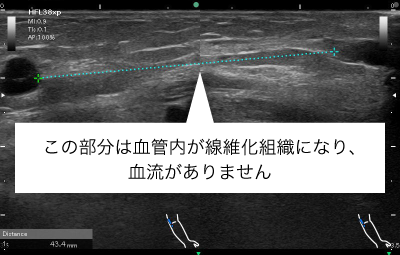

シャント閉塞はしなくても、血流がほとんどないシャント血管部分を長期間放置すると血管内が線維化し部分的に血管が閉塞することがあります。10cm未満のCTOであれば、閉塞した血管の血流を再開させることも可能です。これにより、穿刺部位を広げることが可能となります。